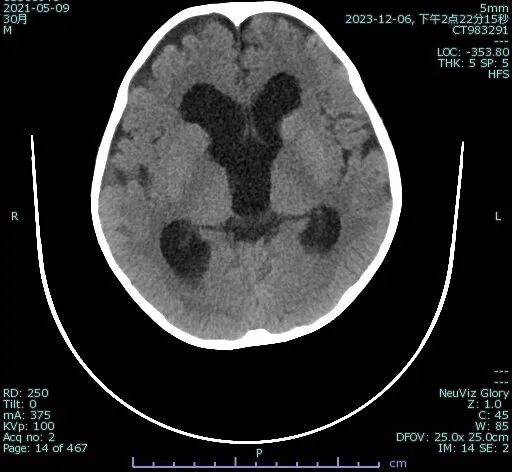

2岁的悠悠(化名)最近间歇性呕吐,家长刚开始以为孩子只是消化问题,可是随着悠悠开始出现头晕、走路不稳、精神差,并伴随间断性肢体无力的现象,家长才慌慌张张赶到医院做了检查。 CT显示:鞍上池囊肿、幕上脑积水。

心急如焚的家长急匆匆来到了郑州大学第三附属医院(河南省妇幼保健院)神经外科。主任医师 张云鹤对悠悠进行了仔细检查后,指着片子对家属说:“看这张片子的构图像不像个‘米老鼠’?正常的片子是不会呈现这种影像的。这两个‘米老鼠’的耳朵,是扩大的侧脑室额角,‘米老鼠’的大鼻子(脸),是囊肿不断长大后,被其撑大的三脑室,这是典型的鞍上池囊肿的影像学表现。”